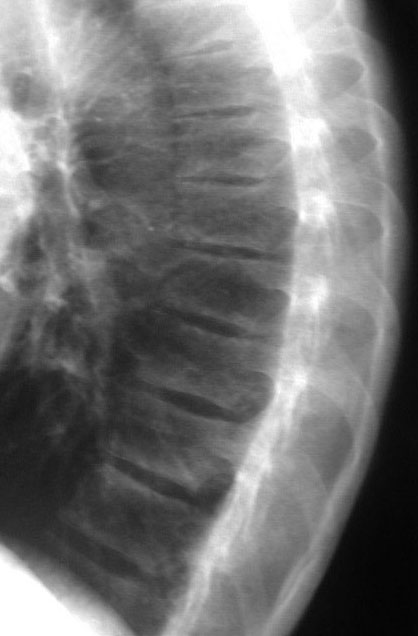

SIGNO DE LA C

Signo de coalición subtalar (fusión calcáneo-astragalina) en la radiografía lateral del tobillo. La «C» se forma por el límite medial de la cúpula talar y el límite posteroinferior del sustentaculum tali.

En la radiografía lateral de tobillo hemos marcado con flechas la «C» que da nombre al signo.

La fusión calcáneo-astragalina (flecha) se comprueba en el corte coronal de TC de tobillo.

Referencia: Lateur LM y cols. Subtalar coalition: diagnosis with the C sign on lateral radiographs of the ankle. Radiology 1994; 193: 847-851.